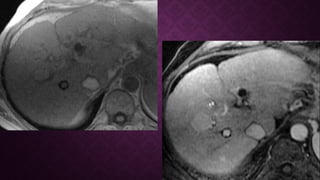

RESONANCIA MAGNETICARESONANCIA MAGNETICA

• T1

• variable

• iso- o hiperintensa del hígado circundante

• hiperintensidad puede deberse a

• grasa intratumoral

• disminución de la intensidad en el hígado

• T1 C + (Gd)

• mejora es generalmente arterial ("hypervascularity")

• "lavado rápido", convirtiéndose en hipointenso para el resto del hígado (96% específico) (esto

se debe a que el suministro a los CHC es predominantemente de la arteria hepática en lugar

de la vena porta)

• la mejora del borde puede persistir (denominada cápsula)

• se ha desarrollado un sistema de clasificación por imágenes ( LI-RADS ) para estratificar

lesiones

RESONANCIA MAGNETICARESONANCIA MAGNETICA •T1 • variable • iso- o hiperintensa del hígado circundante • hiperintensidad puede deberse a • grasa intratumoral  • disminución de la intensidad en el hígado • T1 C + (Gd) • mejora es generalmente arterial ("hypervascularity") • "lavado rápido", convirtiéndose en hipointenso para el resto del hígado (96% específico) (esto se debe a que el suministro a los CHC es predominantemente de la arteria hepática en lugar de la vena porta) • la mejora del borde puede persistir (denominada cápsula) • se ha desarrollado un sistema de clasificación por imágenes ( LI-RADS ) para estratificar lesiones